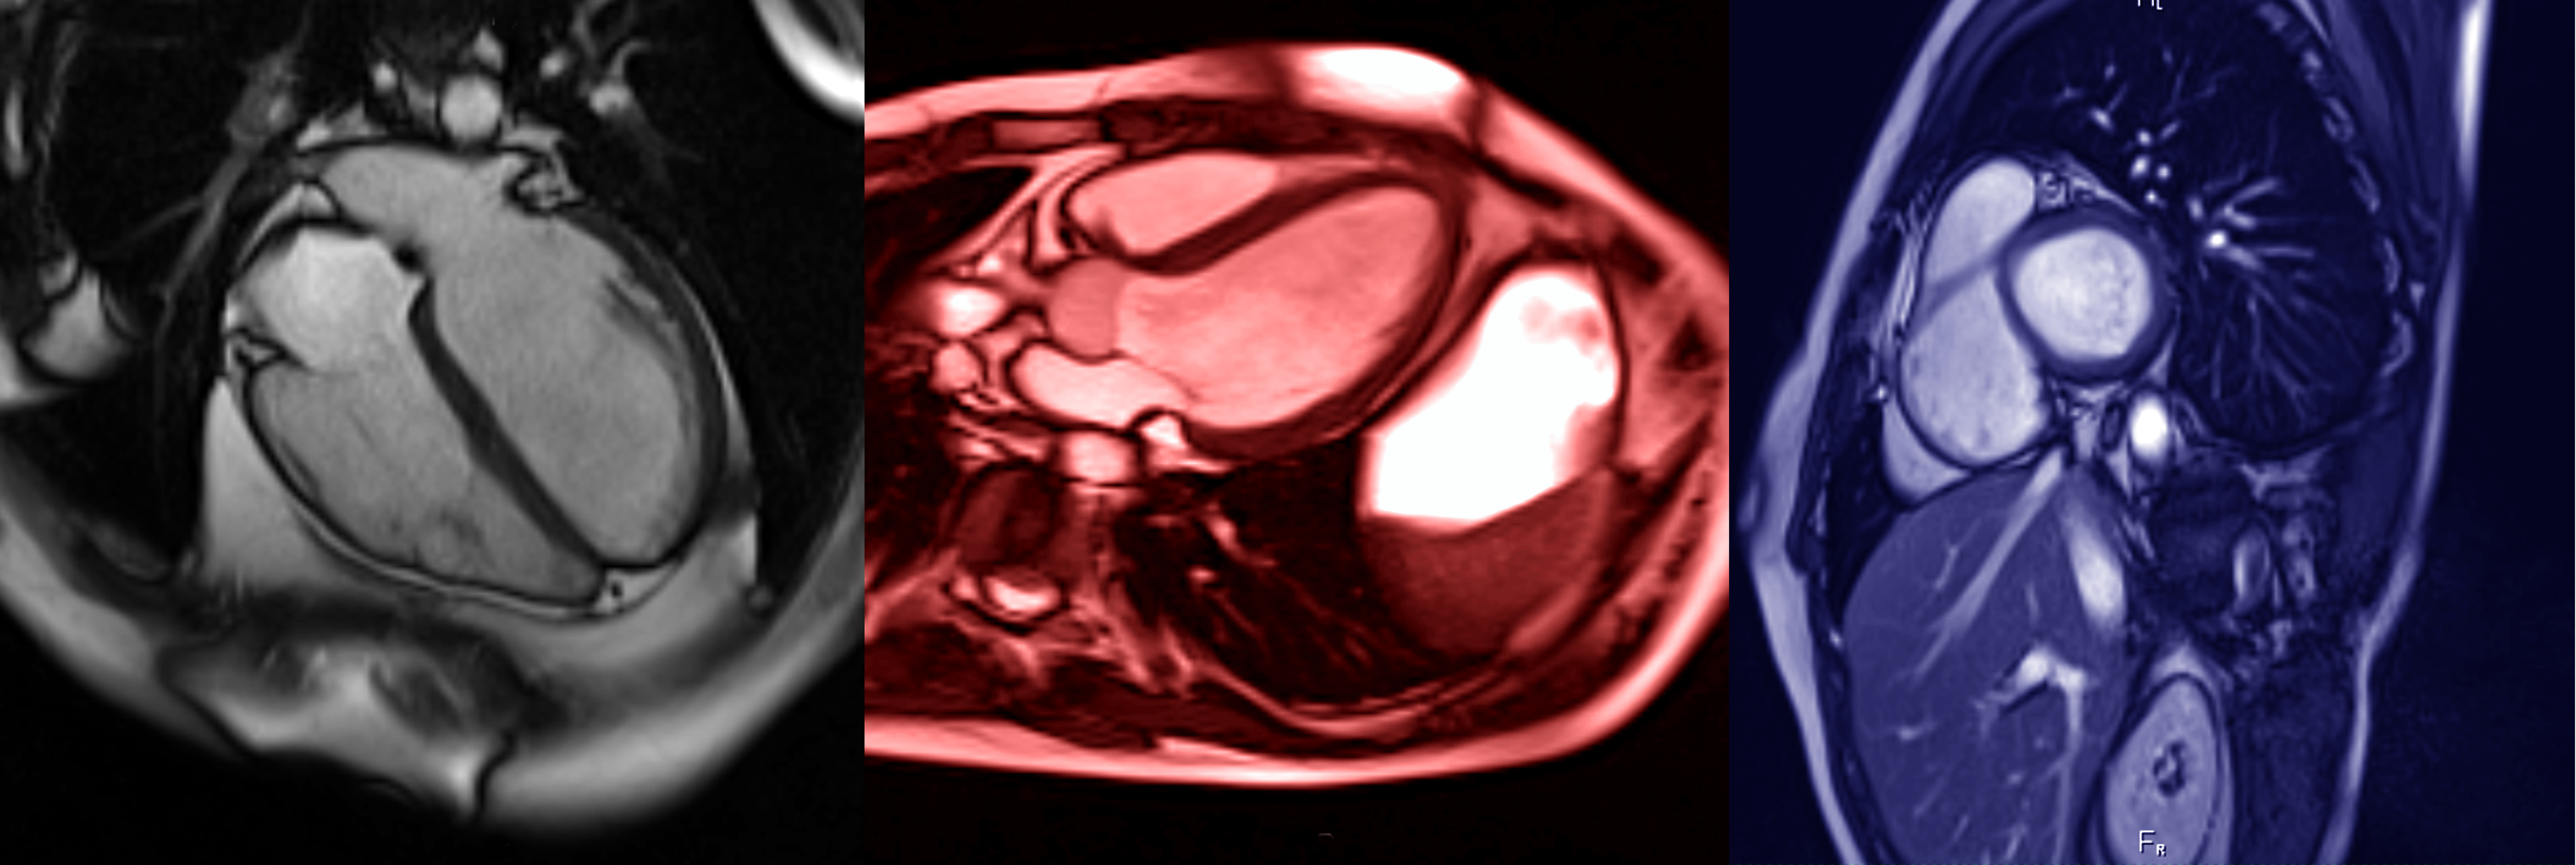

L'imagerie cardiovasculaire est une sous-spécialité de la radiologie qui permet de visualiser l'état circulatoire de l'appareil cardio-vasculaire à des fins diagnostiques, thérapeutiques ou de recherche. Elle permet d’analyser votre cœur et l'anatomie environnante.

Elle est utilisée pour diagnostiquer et gérer les maladies cardiaques, déterminer si une crise cardiaque s’est produite et l’étendue des dégâts, trouver la cause de certains symptômes tels que des douleurs thoraciques et un essoufflement, surveiller le cœur pour évaluer si les traitements fonctionnent.

L’imagerie cardiaque peut être utile pour diagnostiquer et gérer de nombreuses maladies cardiaques.

Les examens comprennent les radiographies, l’échographie, l’IRM et le scanner.